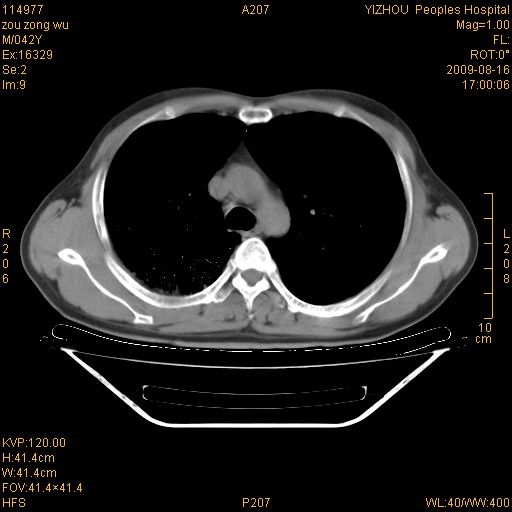

以下是引用zjzjr在2009-8-17 10:42:00的发言:[br]右侧间质性肺炎伴纤维化,右肺下叶肺囊肿伴感染(不除外外伤后引起),右肺野及胸壁软组织\\肝内见多发斑点状,中枪了吧.右侧胸膜肥厚\\粘连.